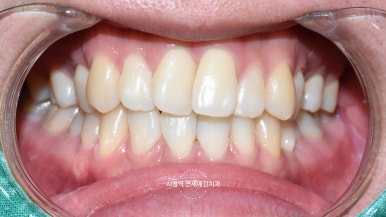

거두절미하고, 백문이 불여일견이니

앞니레진. 저희 치과에서 진행한 앞니 레진치료 사진

전후사진 여러 케이스들을 공개합니다.

[환자분들의 동의를 얻은 사진만 게시합니다.]

다이아스테마(앞니 사이 벌어진 부분) 레진 치료

다이아스테마 레진치료